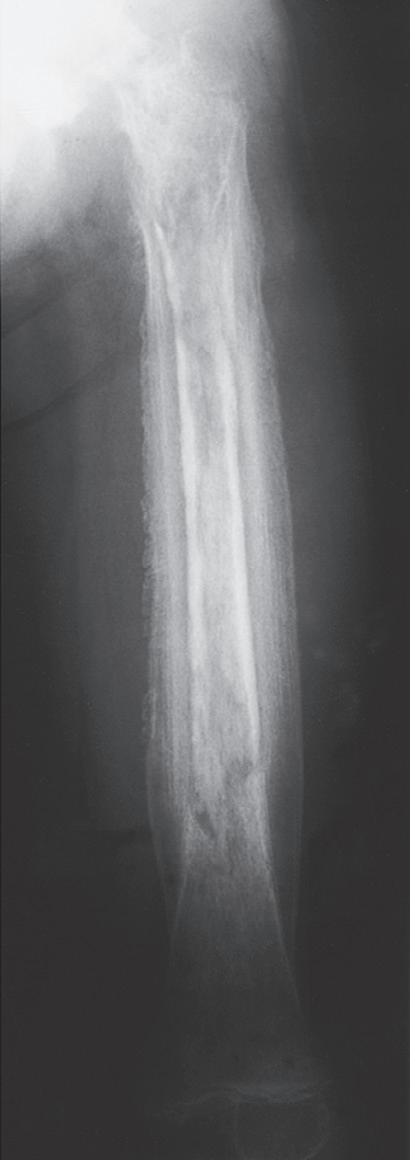

Pediatric bony injuries are more often treated by closed reduction than by open reduction because of the short time to union and the ease of obtaining and maintaining near-anatomic reductions, as well as the potential for remodeling (Fig. 1.8). The quality of anesthesia/analgesia provided to the child is strongly correlated with the quality of the reduction.22

Fig. 1.8 (A) Anteroposterior and lateral radiographs of a 15-year-old boy who sustained a displaced transverse fracture of the diaphysis of his tibia. (B) Follow-up at 4 months shows abundant periosteal healing, although a portion of the fracture line is still evident. It is characteristic for pediatric long bone fractures to heal early with periosteal callus; secondarily, the diaphyseal cortex heals and remodels.

Fig. 1.9 (A) Radiograph of a 7-year-old boy who sustained a fracture of the medial malleolus, as shown in this mortise view. The fracture was treated with closed reduction and application of a long leg cast. (B) Mortise view of the ankle of the same patient 4 years after his injury. The medial malleolus portion of the epiphysis has healed to the metaphyseal area of this Salter-Harris type IV injury. He has not only an incongruous growth plate but also an incongruous ankle joint (arrows). Intraarticular fractures such as this one should be treated with open reduction and internal fixation to anatomically restore both the joint surface and the growth plate.

The most obvious anatomic differences in the pediatric skeleton are the presence of growth plates and the thick periosteum. Growth plate injuries and epiphyseal injuries can lead to growth disturbance that may be significant (Fig. 1.9). Treatment of injury to the growth plate and epiphysis parallels adult intraarticular injuries in that pediatric articular injuries require anatomic reduction to preserve joint function and growth potential. As noted earlier, the periosteum in children is much thicker, more active, less readily torn, and more easily stripped from the bone than in adults. The periosteum helps both in reduction (where intact periosteum on the concavity of the deformity serves as a hinge) and

in maintenance of reduction and contributes immensely to rapid fracture healing. The intact periosteum helps reduce the amount of displacement and is the primary reason for more stable fractures in children.